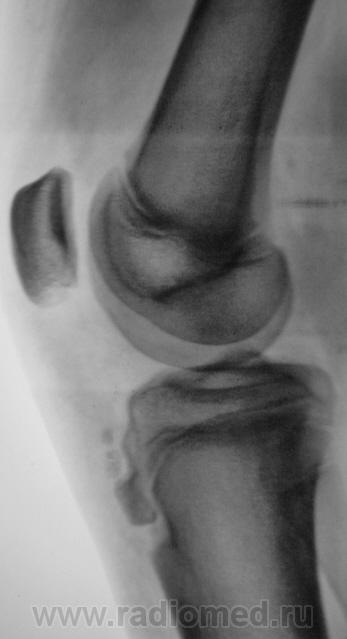

Пациент был направлен на рентгеновское исследования обоих коленных суставов по поводу болеши "Осгут-Шлаттера"

Нет, я был не прав, что утверждал, что на прямой рентгенограмме бугристость не отображается. Мы, на пленке уже вообще не работаем, оказалось, что на "цифре" на прямой отображается и ох, как хорошо.

Да и на пленке отображается )))

Кроме остеохондропатии бугристостей у пациента явная латеропозизия надколенников и бугристостей большеберцовых костей, что свидетельствует о дисплазии мыщелков бедренных костей, вероятнее всего клинически проявляющаяся болями в переднем отделе коленных суставов (под надколенниками).

Интересно было бы посмотреть на аксиальные снимки надколенников. Явно ожидается уплощение медиальных мыщелков и межмыщелковых углублений бедренных костей.